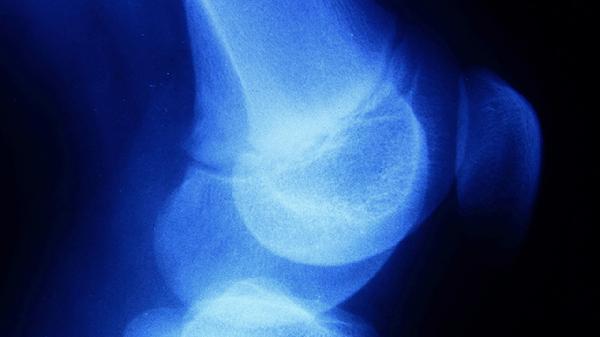

建议定期监测骨龄变化,每半年拍摄左手X光片评估骨骺闭合程度。日常避免负重劳动和过度节食,骑行时调整车座高度防止脊柱受压。可尝试瑜伽中的山式、猫牛式等体式拉伸椎间隙,配合足底按摩刺激生长相关穴位。保持积极心态,身高并非衡量个人价值的唯一标准,青少年时期更应关注综合素质发展。